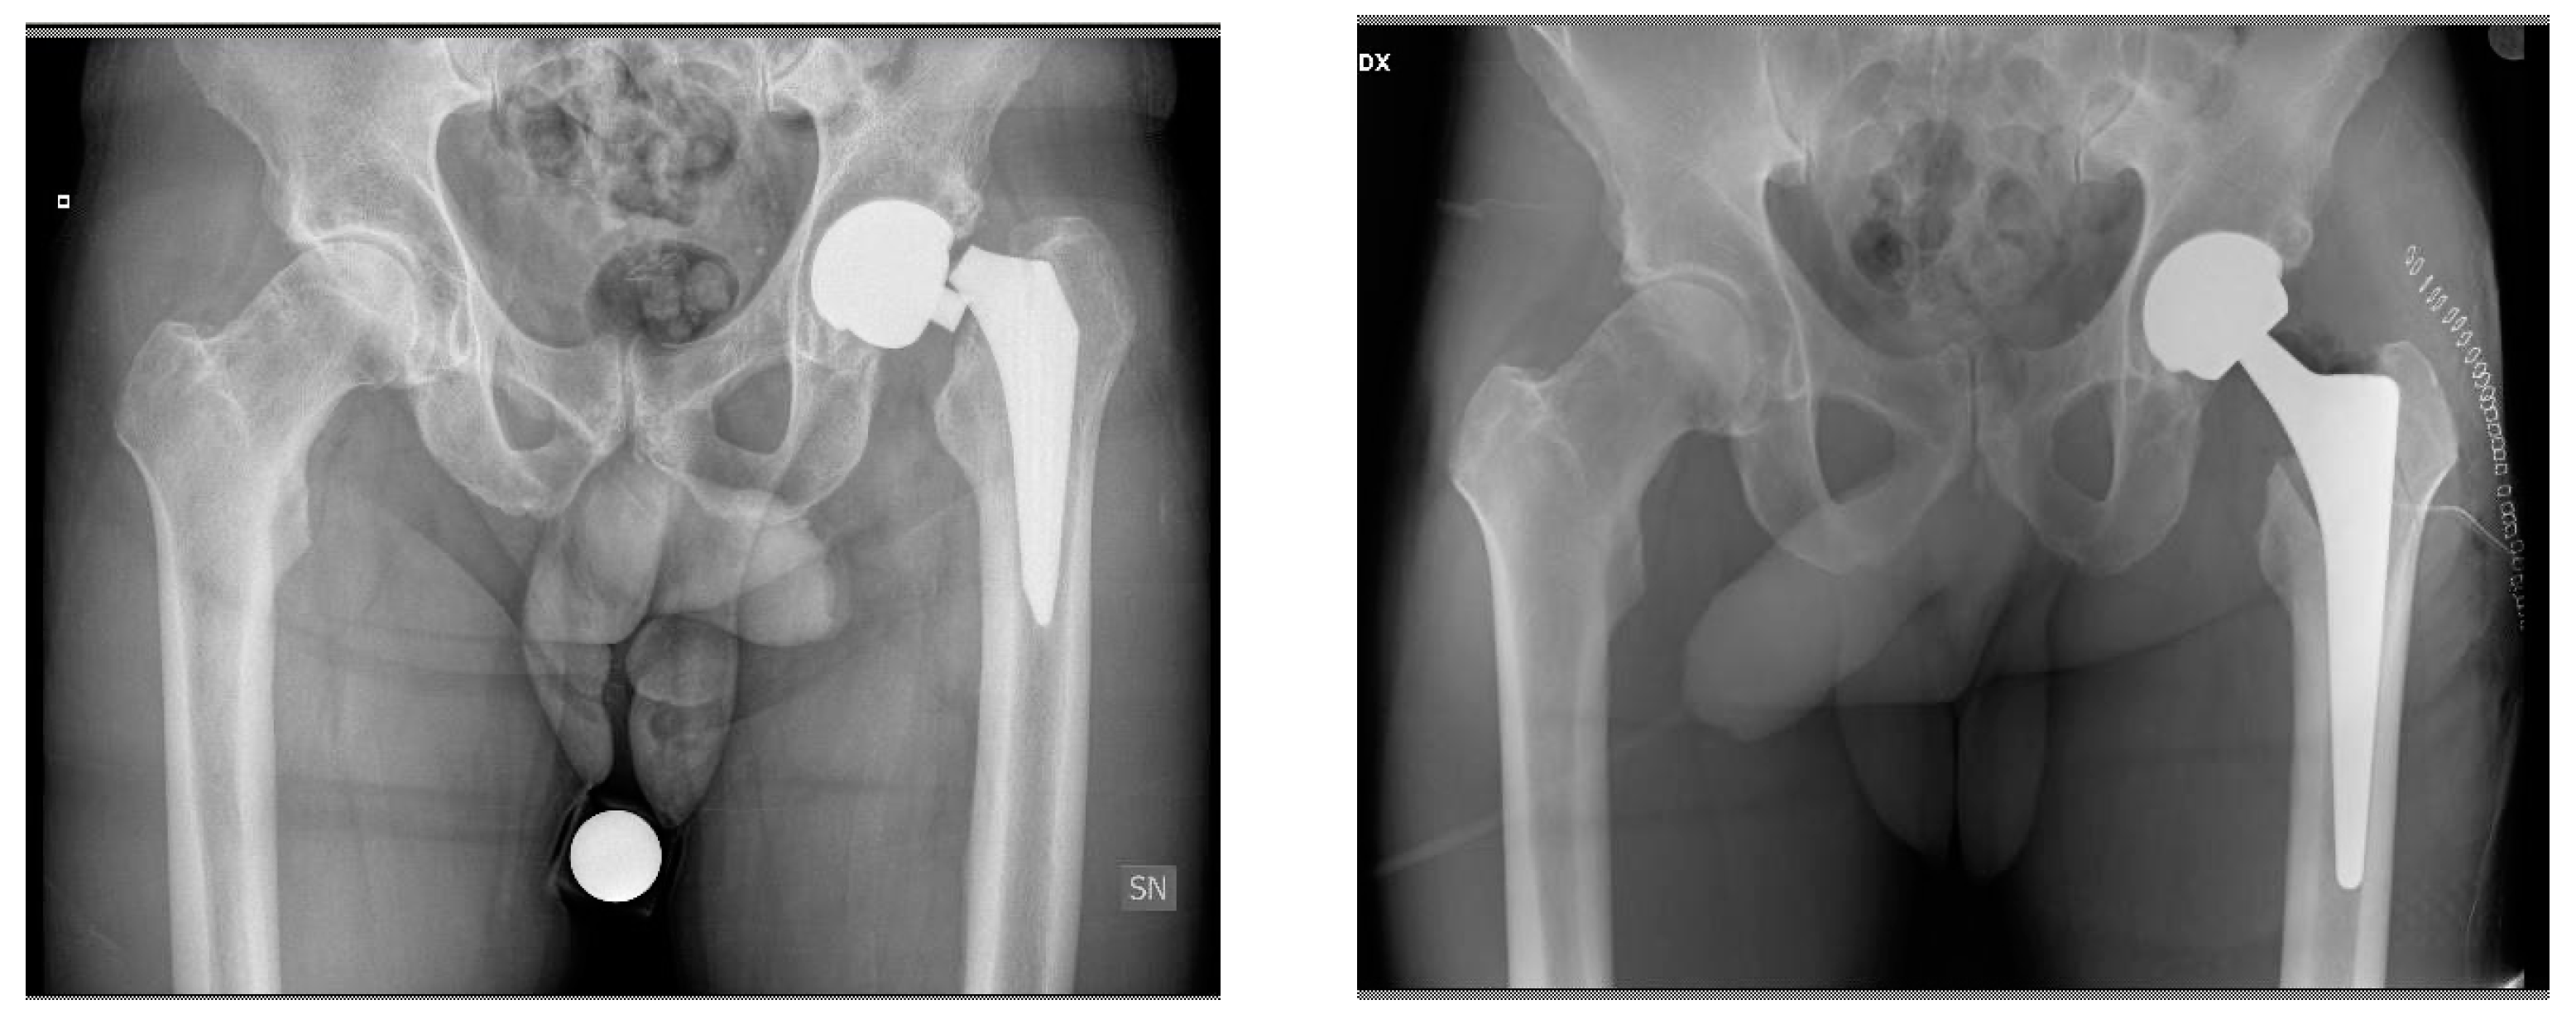

Revision of Failed Short Stems in Total Hip Arthroplasty

2.2. Surgical Technique